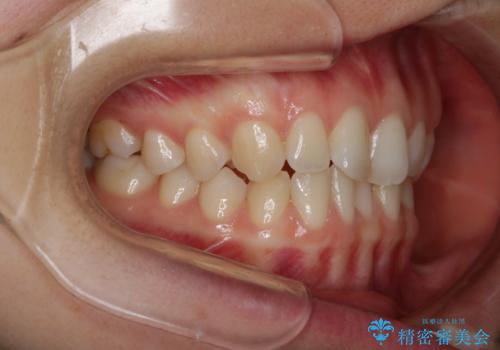

- 上下前歯のがたつきが気になるとご相談にいらした方です。

一見前歯のがたつきだけ改善させれば良い様に見えますが、このがたつきの原因は奥歯の嚙み合わせのズレからくるものであったため、インビザラインFULLで噛み合わせの改善から行っていきました。前歯の角度も改善されたために頑張って唇を閉じる必要がなくなり、横顔のシルエットも綺麗になりました。

前歯のがたつきだけを治そうとした場合、噛み合わせは二の次なってしまう事が多く、せっかく綺麗になった歯並びも後戻りしやすくなります。奥歯の噛み合わせからしっかり機能させることで、長期間にわたって綺麗な歯並びを保ちやすくなります。

インビザライン20時間以上正しく装着していただいたおかげもあり、短期間で治療することが出来ました。